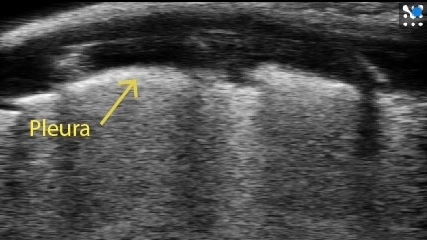

Healthy Lung Characteristic Artifacts:

- Bright pleural line at top

- A-lines - Curved, bright lines between dark rib shadows

Image courtesy of: M.Sc. Niklas Hegemann, Kübler lab, Institute of Physiology, Charité-Universitätsmedizin Berlin & Dr. Jana Grune, Nahrendorf lab, Center for Systems Biology, Massachusetts General Hospital.